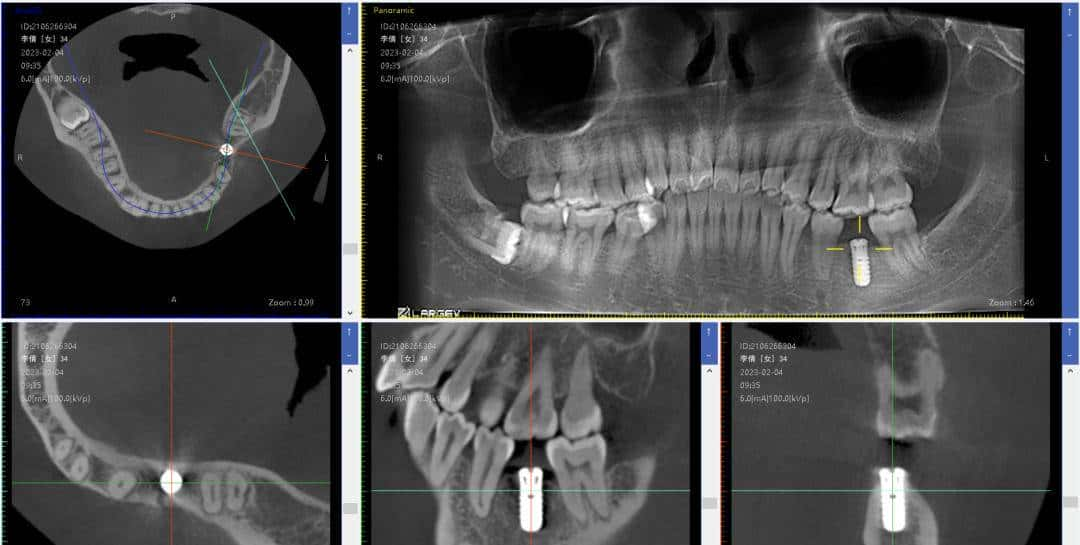

酷酷倩:花得最值得一笔钱就是,一颗种植牙。

缺牙十年,由于不影响吃饭加上太害怕,始终不敢去种植,直到2023年1月,终于鼓起勇气。目前不但吃硬物不用靠单边脸了,并且通过调整了单边咀嚼硬物一年左右后,左右脸不对称也有了改善。太庆幸自己的决定了!▼